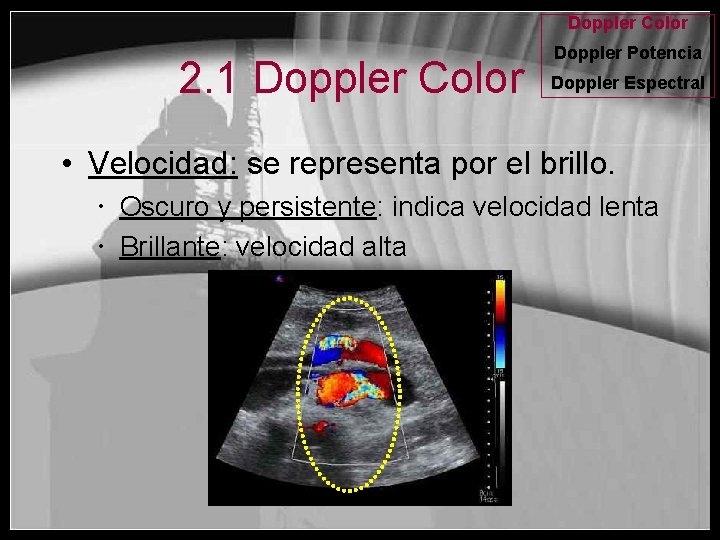

Doppler Color 2. 1 Doppler Color Doppler Potencia Doppler Espectral • Velocidad: se representa por el brillo. Oscuro y persistente: indica velocidad lenta Brillante: velocidad alta